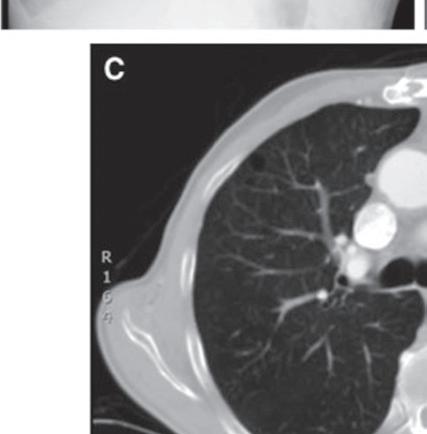

Most DECT datasets can be used to generate additional virtual monoenergetic images (typically between 40 and 60 keV [kilo electron volts]) that have high-contrast enhancement because they are close to the k-edge of the iodine. To minimize contrast streak artifacts and image noise in larger patients, higher keV images ( >70 keV) may be necessary. Iodine or pulmonary blood volume images represent material decomposition images (obtained from subtracting water from contrast-enhanced DECT images) that provide information on distribution of iodine in the lungs or remainder of the chest depending on the selected settings. The absolute iodine concentration expressed as milligrams per milliliter can be calculated from pulmonary blood volume images (Fig. 1.10). One can also generate water or virtual noncontrast images from contrast-enhanced

FIGURE 1.10 Estimation of iodine density in lung cancer. A standard computed tomography image (A) demonstrates an enhancing mass in the right upper lobe, particularly in the anterior aspect of the mass. The absolute iodine concentration expressed as milligrams per milliliter can be calculated from pulmonary blood volume (PBV) images (B)